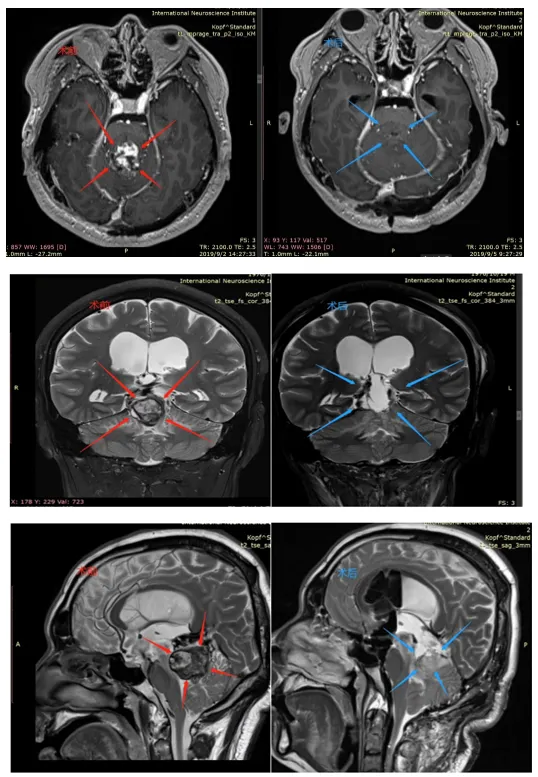

CASE 4:40岁女士-松果体肿瘤

术前(红色):在松果体区域显示出对比度增强的团块,并向下延伸到第四脑室。脑干出现水肿。

术后(蓝色):松果体肿瘤被完整切除,无严重神经功能损伤(术后影像为术中磁共振检查时的瘤腔填充物)

病史摘要:40多岁秦女士,头晕、双眼复视,被发现有“松果体及四脑室占位”,4年间辗转治疗,症状仍无缓解,出现肢体无力等。经历了数次伽马刀及立体定向放射外科治疗,症状反而加重,又出现了走路不稳、视力下降、脑积水等其他更多症状。行“松果体区肿瘤切除术”,但只有小部分肿瘤得到切除,术后症状未见明显好转,并逐渐恶化加重。

手术入路:使用小脑幕上、幕下联合入路来到达肿瘤区域实现全切除

术后情况:术后第2天即拔除气管,自主呼吸正常,身体体征正常,迁出ICU,复视好转。术后5天在专业陪同下床康复锻炼,头晕明显改善,肌力好转。术后18天顺利出院,无新发神经功能缺损。